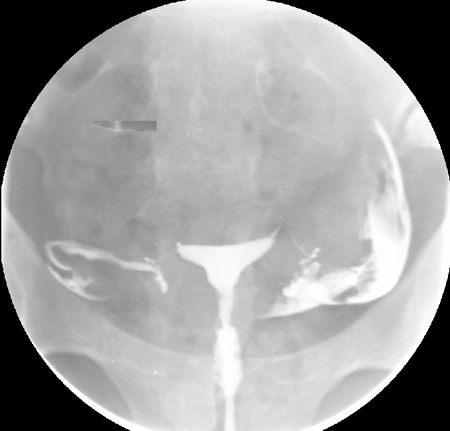

Normal hysterosalpingography (HSG)

From the collection of Dr Jared C. Robins